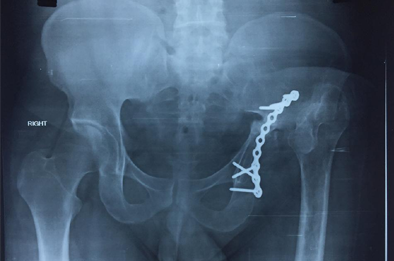

Total Hip Replacement in fracture acetabulum